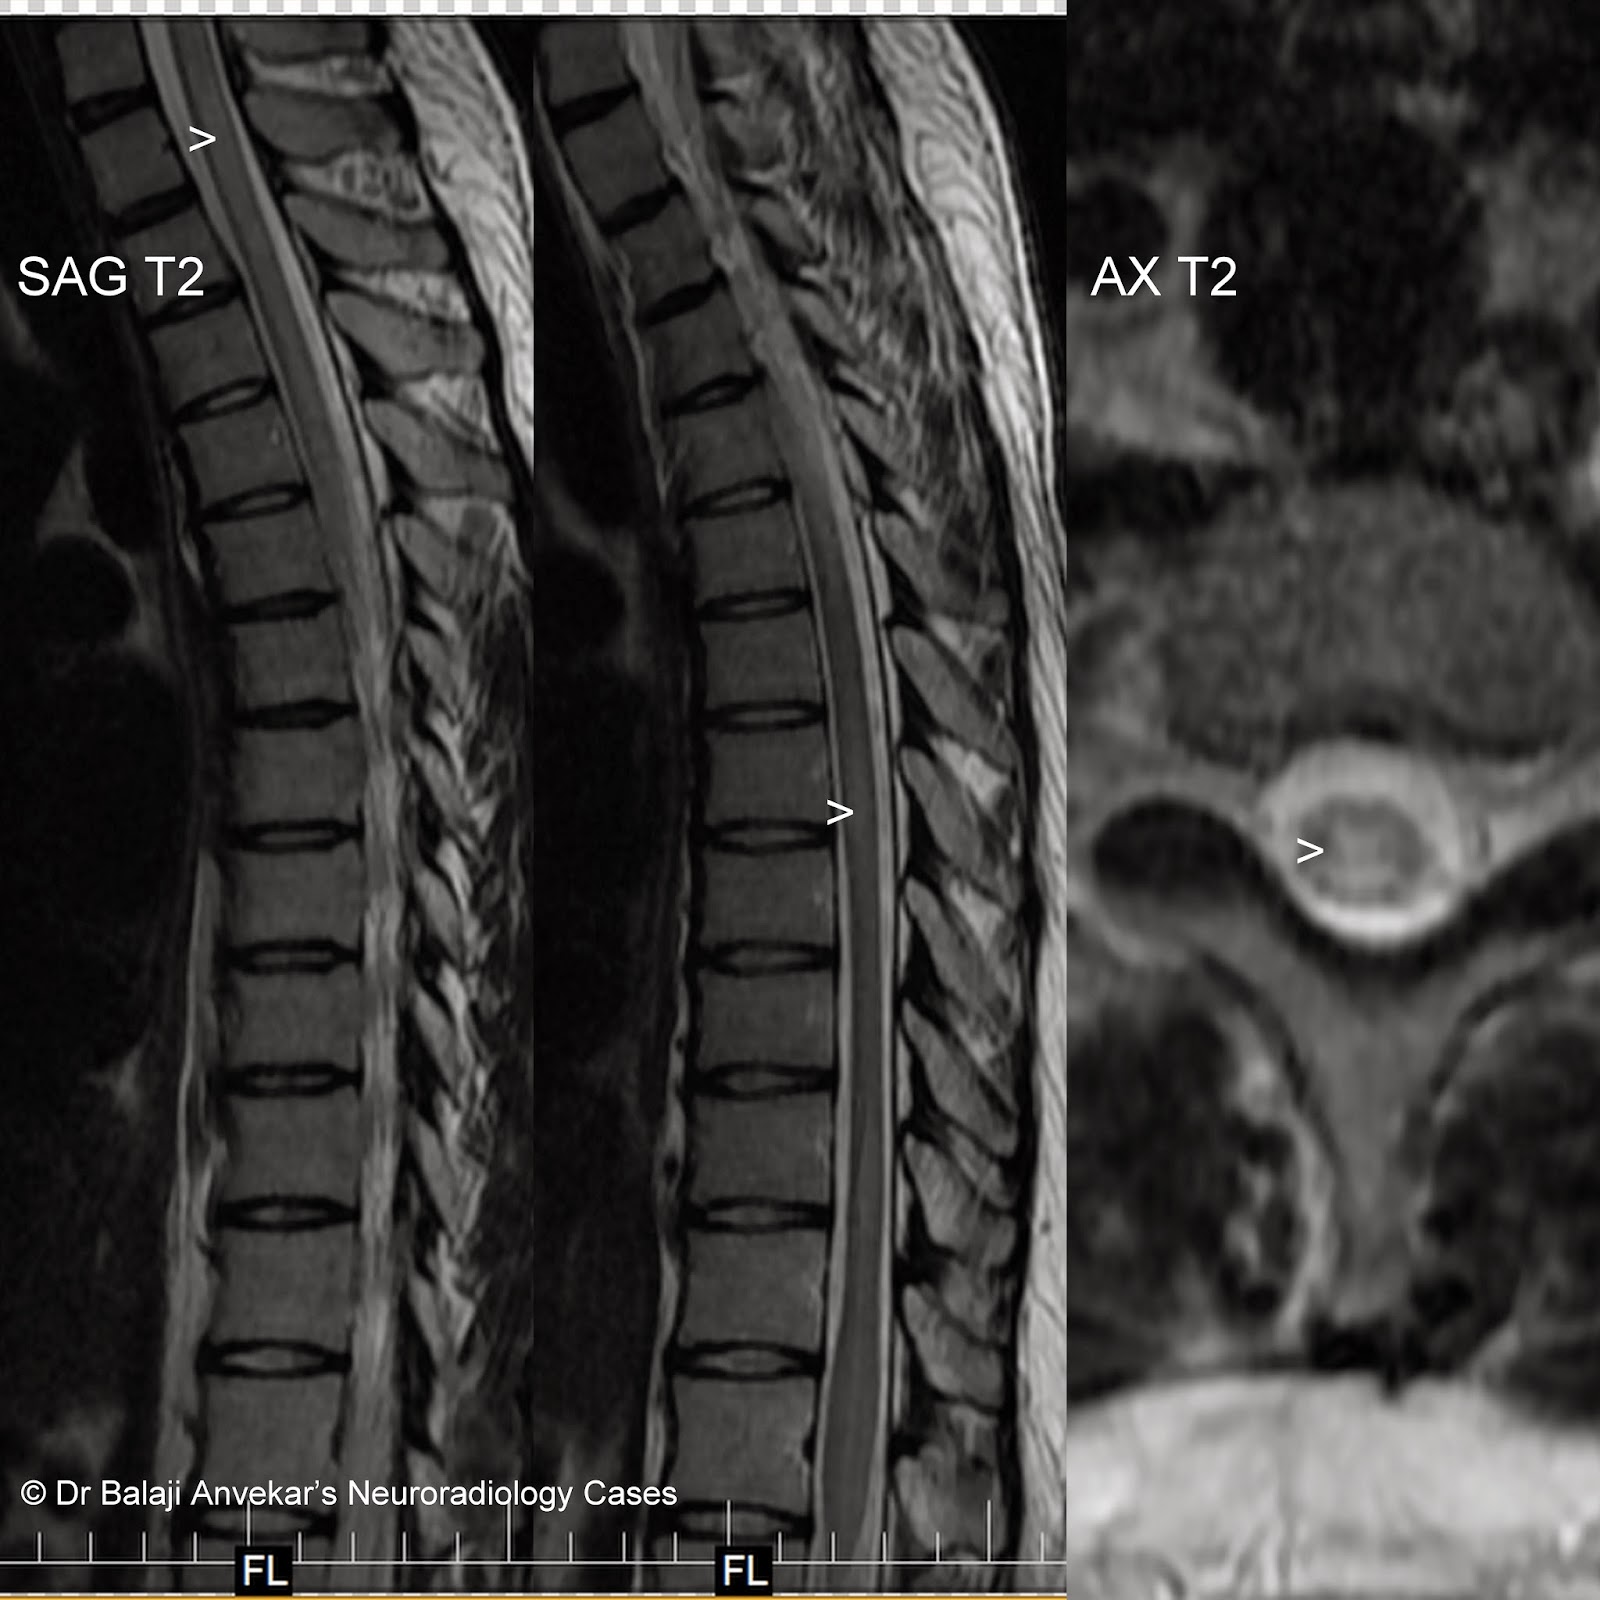

Transverse Myelitis - Longitudinal extensive transverse myelitis—it's not all ... : Transverse implies that the inflammation extends horizontally across the spinal cord.

Transverse myelitis is an inflammation of the spinal cord, the part of the central nervous system that sends impulses from the brain to nerves in the body. Transverse myelitis occurs in adults and children, in males and females and in all races. Transverse myelitis is a neurological condition that happens when both sides of the same section of the spinal cord become inflamed. A fatty tissue called myelin protects these nerve fibers. Partial transverse myelitis and partial myelitis are terms sometimes used to specify inflammation that only affects part of the width of the spinal cord.